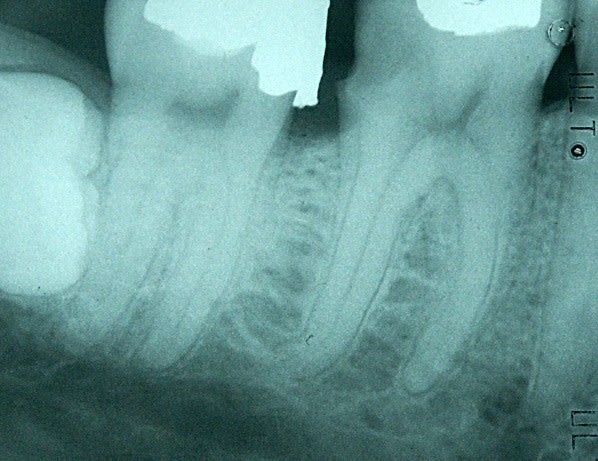

En parlant de F2, c'est le dernier instrument que j'ai cassé (en avril). Deux en toute cette année.

Endo sur un patient bruxomane avec une rétraction pulpaire bien marquée et des triangles dentinaires fortement prononcés.

Le F2 cassé est situé dans le canal DL de la 36 dans le crochet apical.

L'AD m'avait collé en plus une urgence qui n'en n'était pas une (patient casse pied). De ce fait, je me suis retrouvé à la bourre et un temps raccourci d'1/4h pour faire l'endo. Je speedais à mort et paf...! C'est de ma faute, trop de pression apicale + pour gagner du temps j'ai regardé la radio à la lumière du scialytique (où on ne devinait pas le crochet) au lieu du négato.

Dommage car il n'était pas moche ce traitement... (4 canaux).